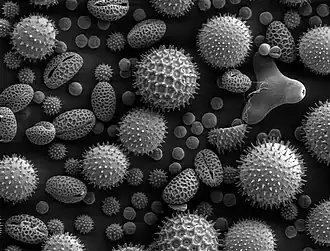

| Partículas de pólen de várias plantas, a causa mais comum de rinite alérgica | |

Rinite alérgica, conhecida popularmente por febre dos fenos, é um tipo de inflamação do nariz que ocorre quando o sistema imunitário tem uma reação excessiva aos alergénios no ar.[6] Os sinais e sintomas incluem congestão ou corrimento nasal, espirros e comichão nos olhos, que se podem tornar vermelhos e inflamados.[1] O muco que escorre do nariz é geralmente límpido. Os sintomas têm geralmente início poucos minutos após a exposição ao alergénio e podem afetar o sono, a capacidade de trabalho e a capacidade de concentração.[2] Nas pessoas alérgicas ao pólen, os sintomas geralmente ocorrem com maior intensidade durante determinadas épocas do ano.[3] Muitas pessoas com rinite alérgica também apresentam asma, conjuntivite alérgica ou dermatite atópica.[2] Os sintomas da rinite alérgica são semelhantes aos da constipação; no entanto, raramente duram mais do que duas semanas e não incluem febre.[3]

O desenvolvimento de alergias é uma combinação de herança genética e de exposição a fatores ambientais. A rinite alérgica é geralmente desencadeada por alergénios ambientais, como o pólen, pelo de animais, pó ou bolor.[3] O mecanismo subjacente envolve a ligação de anticorpos IgE ao alergénio, o que causa a libertação de químicos inflamatórios dos mastócitos, como a histamina.[2] O diagnóstico geralmente tem por base o historial clínico em conjugação com provas de sensibilidade cutânea ou análises ao sangue para detectar anticorpos IgE específicos. No entanto, estes testes apresentam frequentemente falsos positivos.[4]

A febre dos fenos, tal como todas as alergias, é uma resposta exagerada do sistema imunitário a um alergéneo, que geralmente é uma substância inócua e na maioria das pessoas não desencadeia uma resposta imune. Este tipo de resposta é designada por reacção de hipersensibilidade tipo 1.

Nas pessoas alérgicas, o pólen é inspirado e entra em contacto com a mucosa das vias aéreas. Aí, liga-se a anticorpos do tipo IgE que estão na parede de um tipo especial de glóbulos brancos, os mastócitos, fazendo com que sejam libertados vários compostos tais como a histamina, que actuam como mediadores inflamatórios.[17] São estes mediadores que causam os sintomas da febre dos fenos.

A primavera é principalmente a época em que as plantas realizam sua polinização, e se inicia também o processo de floração da maior parte delas. Na maior parte dos casos os grãos de pólen são leves e são transportados pelo vento, dessa forma podem causar problemas respiratórios, desde simples espirros e coceiras até maiores agravos nas vias aéreas.[4]